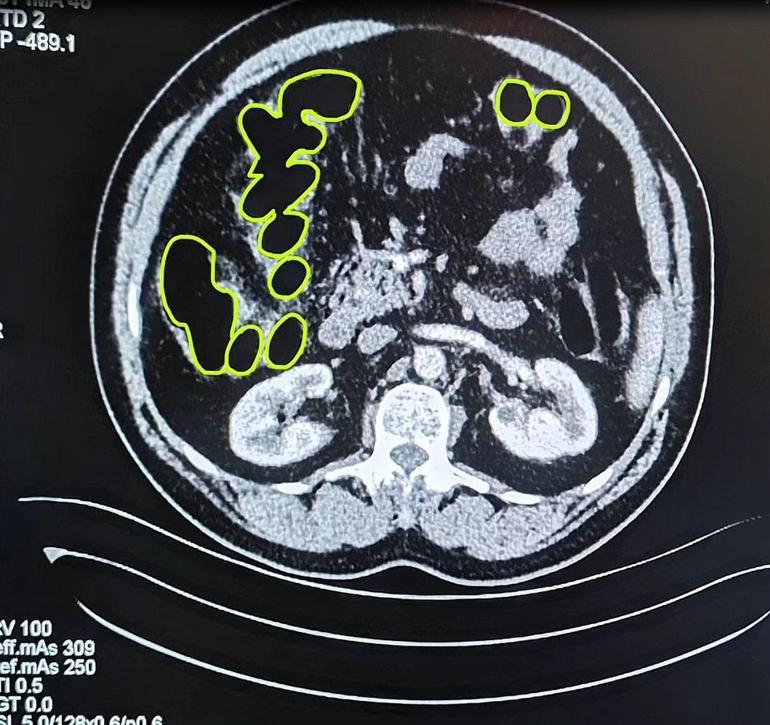

İl Jandarma Komutanlığı ekipleri, İran uyruklu A.O. (51), M.S. (37) ve P.S..'nin (28) ülkelerinden kente uyuşturucu getireceği bilgisine ulaştı. Şüpheliler Kocasinan ilçesi Himmetdede Mahallesi'nde taksi ile kente girmek istediği sırada durduruldu. Araçta yapılan aramada 15 gram esrar, 5 gram bonzai ve 117 adet uyuşturucu hap ele geçirildi. Gözaltına alınan 3 şüpheli muayene olmak üzere Kayseri Şehir Hastanesi'ne getirildi. Röntgen ve ultrason sonrası kontrollerde 3 şüphelinin midesinde uyuşturucu madde olduğu belirlendi. Şüphelilerin yuttukları uyuşturucuları kente sokmaya çalıştıkları tespit edildi. Kapsüller, sağlık ekibinin müdahalesiyle çıkarıldı. Taburcu edilen şüpheliler, İlçe Jandarma Komutanlığı'na götürüldü.